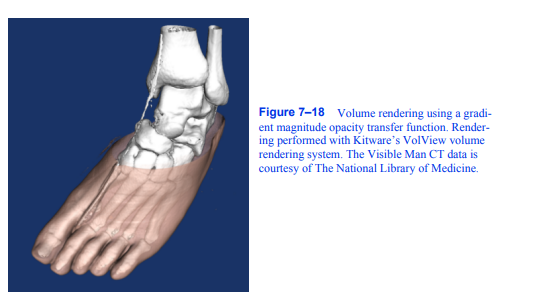

仅根据标量值对卷进行分类通常无法隔离感兴趣的对象。Levoy [Levoy88]引入的一种技术在传递函数的规范中添加了一个梯度幅度维度。使用这种技术,我们可以根据标量值和梯度幅度的组合在体积中指定一个对象。这允许我们定义一个不透明度传递函数,该函数可以在密度范围内的标量值和梯度范围内的梯度范围内针对体素。这对于避免在卷中选择同构区域和突出显示快速变化的区域非常有用。CT扫描如图7 - 18所示

图7-18使用梯度幅度不透明度传递函数绘制体。使用Kitware的VolView体绘制系统进行渲染。可见人CT数据由国家医学图书馆提供。

一只人的脚。体积的急剧变化,如从空气到皮肤,从肉到骨头的转变,都显示出来了。然而,同质区域,如内部肌肉,大多是透明的。如果我们使用高阶插值函数,如三次三次插值,那么我们可以通过计算插值函数的一阶导数来分析计算数据集中任何位置的梯度向量。虽然我们可以将这种方法用于三线性插值,但由于三线性插值的一阶导数在体素边界上不是连续的,因此它可能会产生不可取的伪影。另一种方法是使用有限差分技术来近似梯度向量:

其中表示根据插值函数在数据集中某个位置的标量值,、、和分别是该函数在、、和轴上的偏导数。处梯度的大小就是得到的向量的长度。这个向量也可以归一化得到一个单位法向量。和的选择至关重要,如图7 - 19所示。如果这些值太小,则由公式7-3导出的梯度向量场可能包含高频率,但如果这些值太大,我们将失去数据集中的小特征。